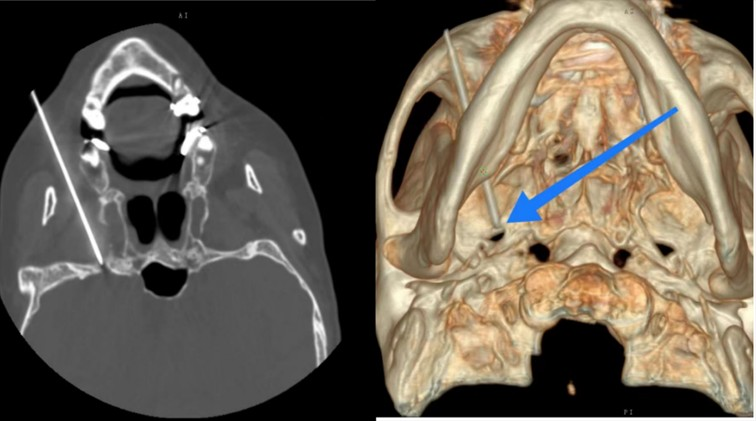

手术在局麻下进行,首先由孙文国主任及其影像介入团队,对卵圆孔进行CT定位、计划穿刺角度,制定分次进针的穿刺计划,由卢斌主任穿刺至卵圆孔,经CT三维重建后可以清楚的显示出穿刺针精准的到达目标位置,三维重建后针尖位置准确,然后进行了感觉与运动神经测试,最后通过针尖端向神经纤维传达射频电流,选择性的射频调控三叉神经病损支神经根到达止痛的目的,手术创口小,痛苦少,仅一个小时就顺利完成。